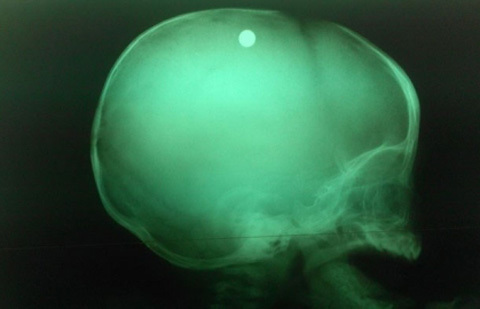

| Viên đạn trong đầu bé trai 6 tuổi qua chụp X-quang- ảnh BV nhi đồng 2. |

Các bác sĩ đã nhanh chóng xác định đây là trường hợp bị thương ở sọ não do hỏa

khí gây ra, và cần phẫu thuật gấp vì kết quả chụp X- quang cho thấy viên đạn vẫn

còn nằm trong sọ của bé.

Sau ca phẫu thuật, bệnh nhi đã được chuyển xuống khoa hồi sức tích cực. Hiện bé đã có thể mở mắt nhưng vẫn còn phải thở máy , có những cơn co gồng và yếu nửa người bên trái. Theo bác sĩ Đặng Xuân Vinh, viên đạn nằm trong nhu mô não, cách xương sọ 2cm.

“Đạn được bắn thẳng vào não. Đường đi của viên đạn này từ chẩm trái xuyên qua xương sọ vào nhu mô não, rồi lên đỉnh trái, cuối cùng chuyển hướng sang đỉnh phải đầu. Vì thế nhu mô não của bệnh nhi này bị tàn phá nặng, kèm xuất huyết não” - bác sĩ Vinh cho hay.